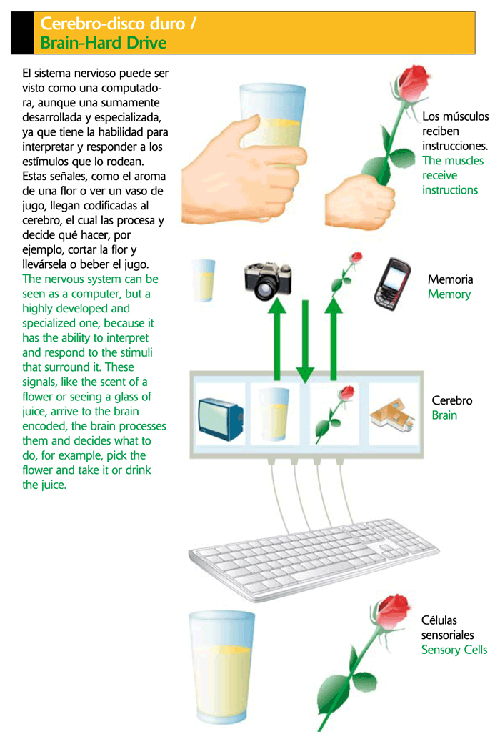

Sistema nervioso:

Es una red compleja de células y nervios por medio de los cuales se transmite información desde el cerebro y la médula espinal a las diferentes partes del cuerpo como por ejemplo el movimiento, sensaciones, etcétera.